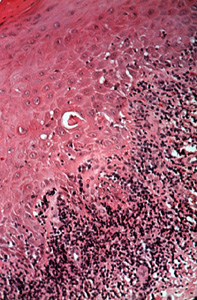

Microscopa del liquen plano.

Los rasgos microscópicos del liquen plano son la hiperqueeratosis, la acantosis focal y una reacción inflamatoria que abraza al epitelio y no se extiende a los tejidos más profundos.

Con un aumento más potente se observa que la inflamación es casi completamente de naturaleza linfocítica.

Hay a veces degeneración hidrópica del epitelio en que las células inflamatorias pueden extenderse.